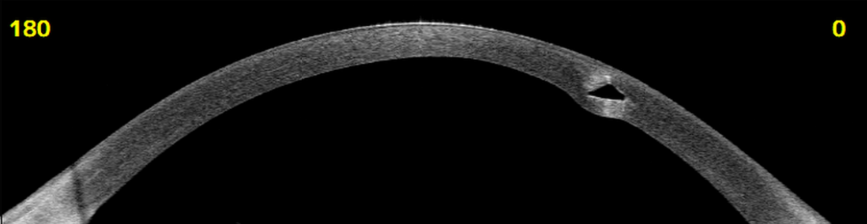

3. Intacs

Intacs zijn kleine, kunststof implantaten die in de periferie van het hoornvlies worden geplaatst. Deze implantaten helpen om de kegelvorm van het hoornvlies te corrigeren, wat kan helpen bij het verbeteren van het gezichtsvermogen en het verminderen van de behoefte aan brillen of contactlenzen. Tube Intacts